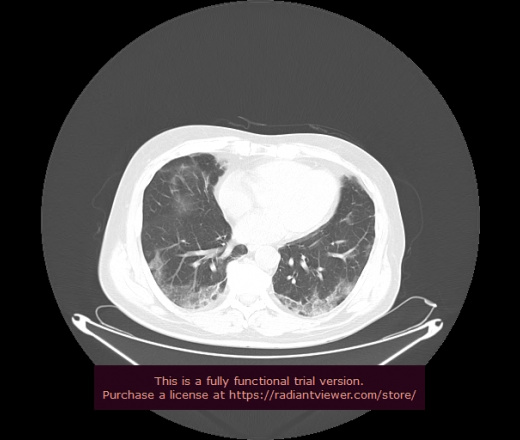

Уважаемые коллеги, если имеется интерес, сможете ли Вы спрогнозировать дальнейшее +-одинаковое течение процесса у 4 данных разных пациентов? Зацепиться где-то можно очень просто, где-то нельзя.